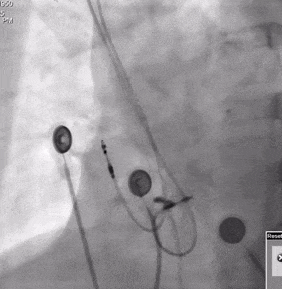

术后植入位点

图11

术后即刻参数QRS:101ms,达峰时间:64ms,SV:39ms。